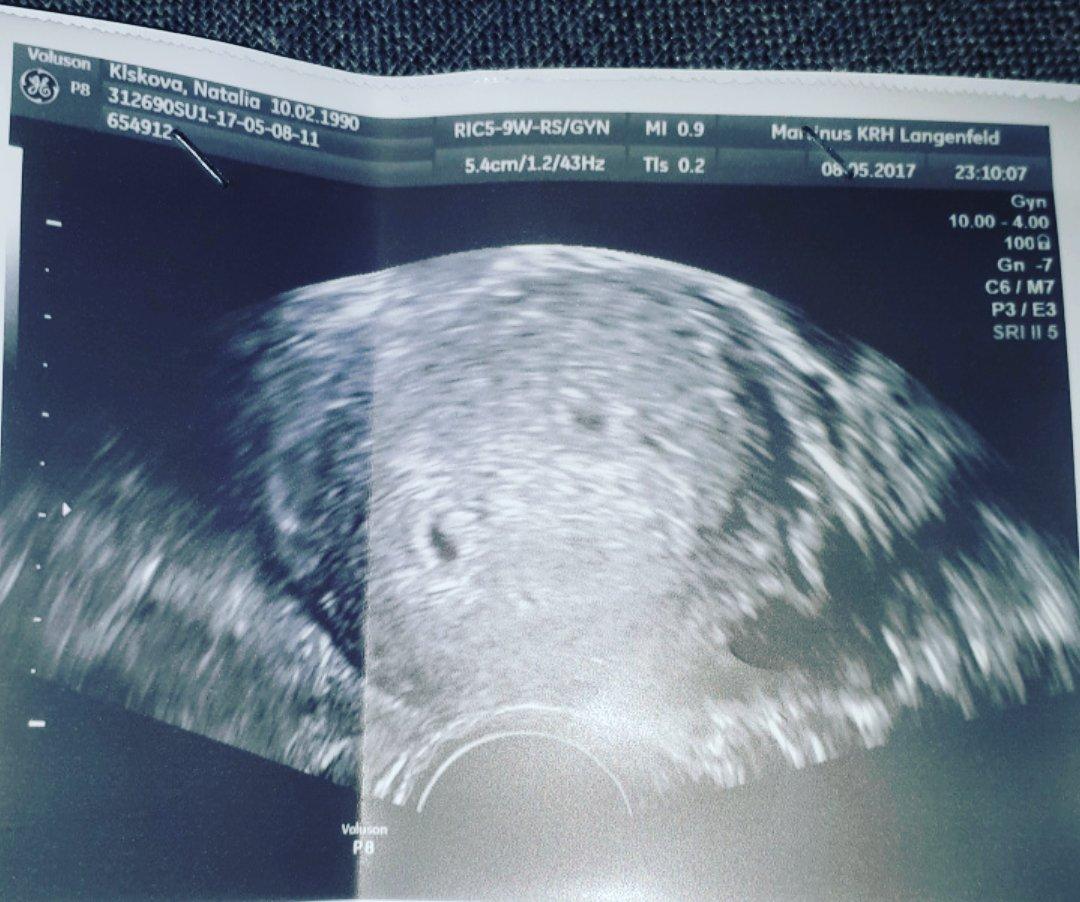

😂 len oni vzdy popletia priezvisko. Zijem v Nemecku 😂 ale dakujrm za pobavenie a gratulaciu 😘

@natalysb Odpadnem a gratulujem zaroven!...WAU, ze dvojicky, to bol aj muz prekvapeny, co?...No tesim sa s vami, dolezite je, ze babätka su tam, kde byt maju a nech sa len pekne obe vyvijaju...Ty to zvladnes, kazda matka to zvladne, ked to takto necakane pride - ze dvojicky...Prajem Ti, nech je to parik...Uzivaj tehulkovanie a som zvedava, ci pridas fotecku, ked bude krasne vidiet oba drobceky...Je to zazrak, v Tvojom pripade dvojnasobny 😉

@natalysb Gratulujem ze WAAAw Dvojickyy teeda moj manzel vzdy tuzil po dvojickach.. sa tesim s tebou neboj sa to zvladnete spolu a tes sa nato.ved mas aj maminu aj svokru a znamych..ktori ti s babetkami pomozu neboj. daj foto ked budu vecsie cem vidiet potom este som nevidela fotku dvojcatiek v brusku ked su uz vecsie.. Drzim Ti palce.